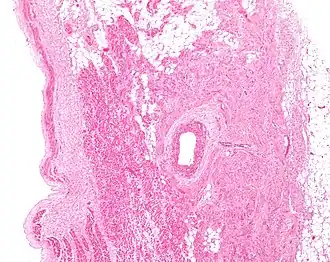

Low magnification micrograph of a sinoatrial node (central on image), surrounding the sinuatrial nodal artery (on lumen in the image). H&E stain. | |

The sinoatrial node surrounds the sinoatrial artery, which can run centrally (in 70% of individuals) or off-center within the node.[4]